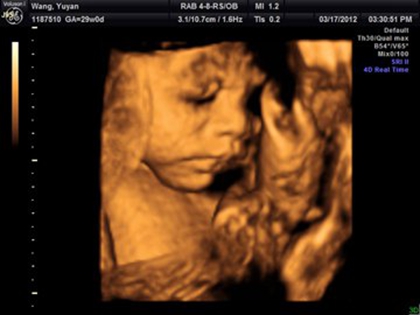

四维胎儿手呈握拳状一般都是男孩吗?

这个说法也是没有科学依据的,宝宝在妈妈的体内会胎动,并且四肢都是可以活动的,宝宝在子宫内手握拳是非常正常的现象,不管是男女宝宝都是这样的,并不能来判断男女。

许多婴儿在妈妈的子宫腔中都是有四肢、手脚有变小的变动,是正常情况,胎儿双手呈握拳状也是正常的。如果有特殊情况,医生一般都会及时通知,也有很大可能是宝宝是检查时处于睡眠状态。也可以根据检测出的各个数据来判断胎儿的发育情况。

男孩一般胎儿四维手呈握拳状